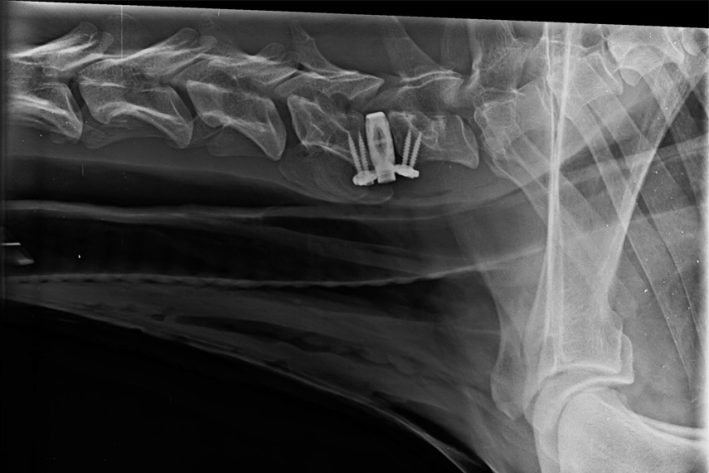

Chirurgische Korrektur des Wobbler-Syndroms

Chirurgische Korrektur des Wobbler-Syndroms: die Instabilität zwischen dem 6. und 7. Halswirbel wurde mit einem Implantat stabilisiert.